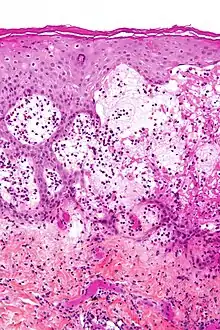

Pemphigoid gestationis (PG), also known as gestational pemphigoid, is an autoimmune variant of the skin disease bullous pemphigoid, that first appears in pregnancy.[3] Symptoms include blisters, small bumps, hives, and intense itching.[1] It usually starting around the belly button before spreading to the chest and limbs; with the head, face, and mouth being spared.[1][4] Onset is usually in mid-pregnancy to shortly after delivery.[1][5]

It is caused by antibodies against the mother's own skin, resulting in skin layers splitting and forming blisters.[4] It is possibly triggered by some placenta cells entering the mother's blood.[4] Risks include molar pregnancy and choriocarcinoma.[1] It does not spread between people and does not run in families.[4] It typically lasts six months and can reoccur in future pregnancies, menstrual periods, and from birth control pill.[1] In some people, it persists long-term.[1] Diagnosis is based on progression of symptoms, blood tests, and skin biopsy with immunofluorescence.[6][5] It can resemble pruritic urticarial papules and plaques of pregnancy (PUPP), erythema multiforme, drug reactions and blistering scabies.[1]

It presents with tense blisters, small bumps, hives and intense itching, usually starting around the belly button before spreading to chest and limbs in mid-pregnancy or shortly after delivery.[1] The head, face and mouth are not usually affected.[4]

Pemphigoid gestationis is an autoimmune variant of the skin disease bullous pemphigoid, and first appears in pregnancy.[3]

Circulating complement-fixing IgG antibodies attach to the lamina lucida resulting in the skin layers splitting and forming blisters, possibly triggered by some placenta cells entering into the mother's blood.[1] The triggering antigen, transmembrane collagen XVII, is part of the baby's membrane cells that encourage the movement of placental cytotrophoblastic cells.[1] The disease appears to be triggered by female hormones.[1] It can recur in subsequent pregnancies, menstrual periods and oral contraceptive pill.[1] A molar pregnancy and choriocarcinoma can provoke it.[1]